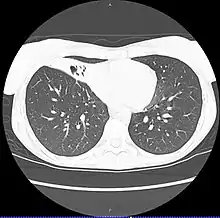

| CT scan of patient with right middle lobe aspiration and Mycobacterium avium infection consistent with Lady Windermere syndrome | |

MAC usually affects patients with abnormal lungs or bronchi. However, Jerome Reich and Richard Johnson describe a series of six patients with MAC infection of the right middle lobe or lingula who did not have any predisposing lung disorders.[17][18]

The right middle lobe and lingula of the lungs are served by bronchi that are oriented downward when a person is in the upright position. As a result, these areas of the lung may be more dependent upon vigorous voluntary expectoration (cough) for clearance of bacteria and secretions.

Since the six patients in their retrospective case series were older females, Reich and Johnson proposed that patients without a vigorous cough may develop right middle lobe or left lingular infection with MAC. They proposed this syndrome be named Lady Windermere syndrome, after the character Lady Windermere in Oscar Wilde's play Lady Windermere's Fan. However, little research has confirmed this speculative cause.[19]

- Chest X-ray or CT scan showing evidence of right middle lobe (or left lingular lobe) lung infection